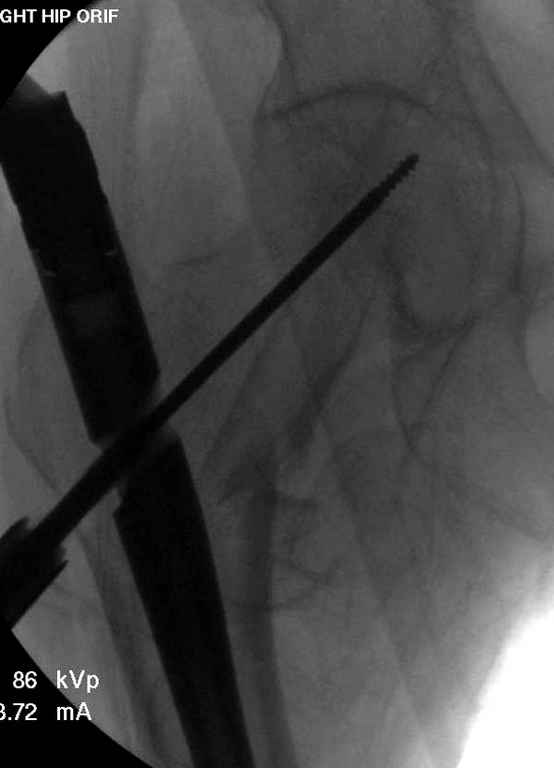

В приложении похожий пример, к счастью, пациентка появилась не после, а "за полчаса" до протрузии. Пересинтезировали с исправлением ошибок.